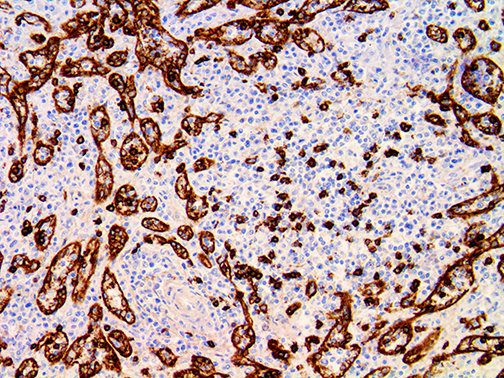

It is the ICU physician who is most likely to witness one of the deadliest manifestations of the abnormal immunological response, the cytokine storm syndrome (CSS). This response is also referred to by some as the cytokine release syndrome (CRS). CSS is characterized by continuous activation and expansion of macrophage and lymphocyte populations, which secrete large amounts of cytokines, causing the cytokine storm. This massive cytokine release is akin to hemophagocytic lymphohistiocytosis (HLH) disease, a syndrome characterized by initial unchecked and persistent activation of cytotoxic T lymphocytes and NK cells.

Clinical and laboratory manifestations of HLH include fever, enlarged liver and/or spleen, neurologic dysfunction, coagulopathy, liver dysfunction, cytopenias (i.e., low levels of erythrocytes, leukocytes, and/or platelets), hypertriglyceridemia, hyperferritinemia, hemophagocytosis, and eventually diminished NK cell activity as the immune system becomes progressively paralyzed. HLH can be familial (primary HLH) or secondary to another disease process (sHLH), such as rheumatic disease, in which it is referred to as macrophage activation syndrome (MAS, characterized by elevated ferritin).

This activation induces inflammatory monocytes to highly express IL-6, starting a localized and then systemic cascade effect that results in hyperproduction of IL-6, which accelerates the inflammatory process. Because IL-6 also increases vascular permeability, excessive levels cause blood vessels to become very leaky. This, along with clotting factors released from vascular endothelial cells, stimulates the coagulation cascade, resulting in microthrombosis (tiny clots), which leads to ischemia and tissue death of the kidney, intestines, heart, liver, brain and extremities.